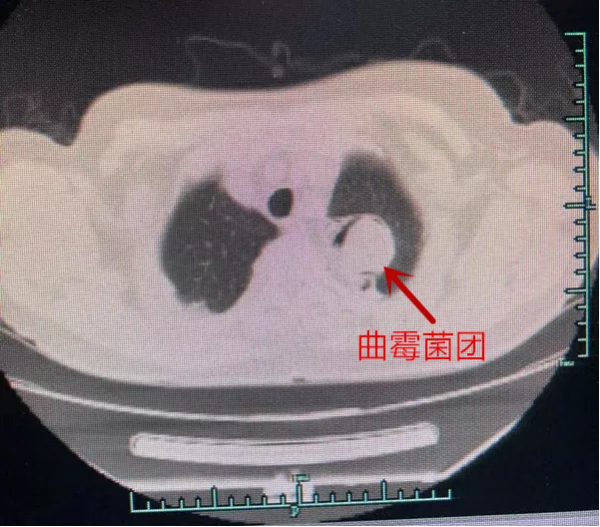

因為麴黴菌的感染和侵蝕,章阿姨左肺上葉已經出現了一處雞蛋大小的空洞,而且正在慢慢變大,再發展下去可能整個左肺都要“淪陷”!馮興醫生立刻予以抗真菌藥治療,使之在肺內形成了穩定的麴菌球團,並安排住進病房,準備擇期手術。

開啟胸腔後,醫生們發現章阿姨的左側全胸腔粘連,於是先用電凝鉤超聲刀小心翼翼分離粘連,儘可能將胸頂和腫物囊壁分離。終於,他們在左肺上葉發現了一個直徑約5cm大小的窟窿,裡面堵著一個青灰色豆腐渣樣的“雞蛋”,一陣惡臭味襲來。

折磨章阿姨10多年的罪魁禍首被“揪”出來了,就是這麴黴菌球!